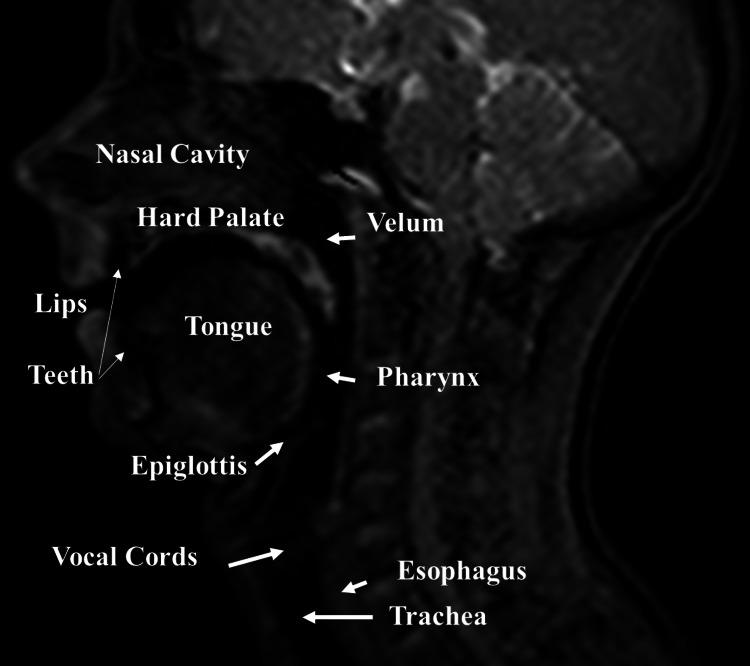

The five osteopathic models recognized by the American Association of Colleges of Osteopathic Medicine guide clinicians in the evaluation and therapeutic choice which must be the most appropriate concerning the patient's needs. Skeletal muscles represent an important interpretation, such as screening and treatment, on which these models are based. A muscle district that is not considered by the usual osteopathic practice is the tongue. The lingual complex has numerous functions, both local and systemic; it can adapt negatively in the presence of pathology, just as it can influence the body system in a non-physiological manner if it is a source of dysfunctions. This paper, the first of its kind in the panorama of scientific literature, briefly reviews the anatomy and neurophysiology of the tongue, trying to highlight the logic and the need to insert this muscle in the context of the five osteopathic models. The clinician's goal is to restore the patient's homeostasis, and we believe that this task is more concrete if the patient is approached after understanding all the contractile districts, including the tongue.

美国整骨医学院协会认可的五种整骨模型指导临床医生进行评估和治疗选择,这些选择必须最符合患者的需求。骨骼肌是这些模型所基于的重要解释内容,例如筛查和治疗。舌部是常规整骨疗法通常不考虑的一个肌肉区域。舌复合体具有众多局部和全身功能;在出现病理情况时它会产生负面适应,同样,如果它是功能障碍的来源,也会以非生理方式影响身体系统。本文是科学文献领域的同类首篇文章,简要回顾了舌部的解剖学和神经生理学,试图突出将这块肌肉纳入五种整骨模型背景下的逻辑和必要性。临床医生的目标是恢复患者的内环境稳定,我们认为,如果在了解包括舌部在内的所有收缩区域后对患者进行治疗,这项任务会更切实可行。